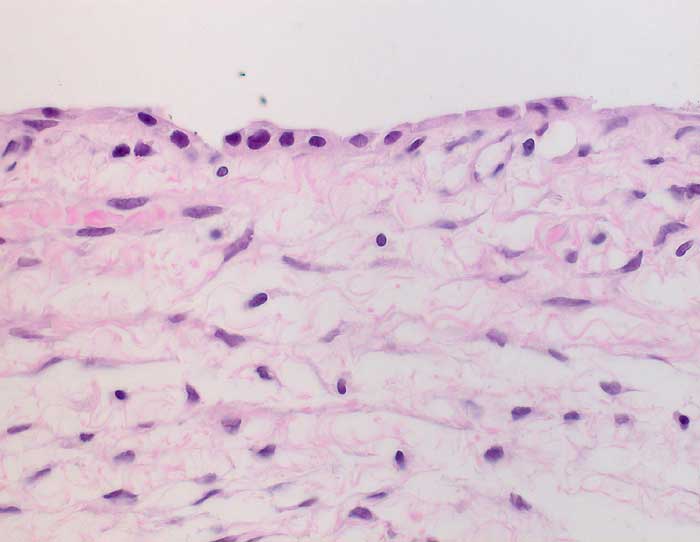

Seröses Zystadenom des Ovars

Der Ausstrich ist zellarm. Die Epithelien sind kubisch bis niedrig-zylindrisch und einzeln oder in flach ausgebreiteten Verbänden gelagert. Die Zellgrenzen sind weniger scharf als beim muzinösen Zystadenom. Die Kerne sind rund und das Chromatin ist fein granulär. Nukleolen sind klein oder fehlen. Das Zytoplasma enthält keinen Schleim und ist nicht vakuolisiert. Der apikale Zellrand trägt Zilien, was das seröse Zystadenom von Granulosazellen einer Follikelzyste unterscheidet. Die Zystenflüssigkeit enthält neben Epithelzellen Schaumzellen, Hämosiderin und ältere Blutbestandteile. Unten werden zwei verschiedene Fälle mit histologischer Korrelation gezeigt.